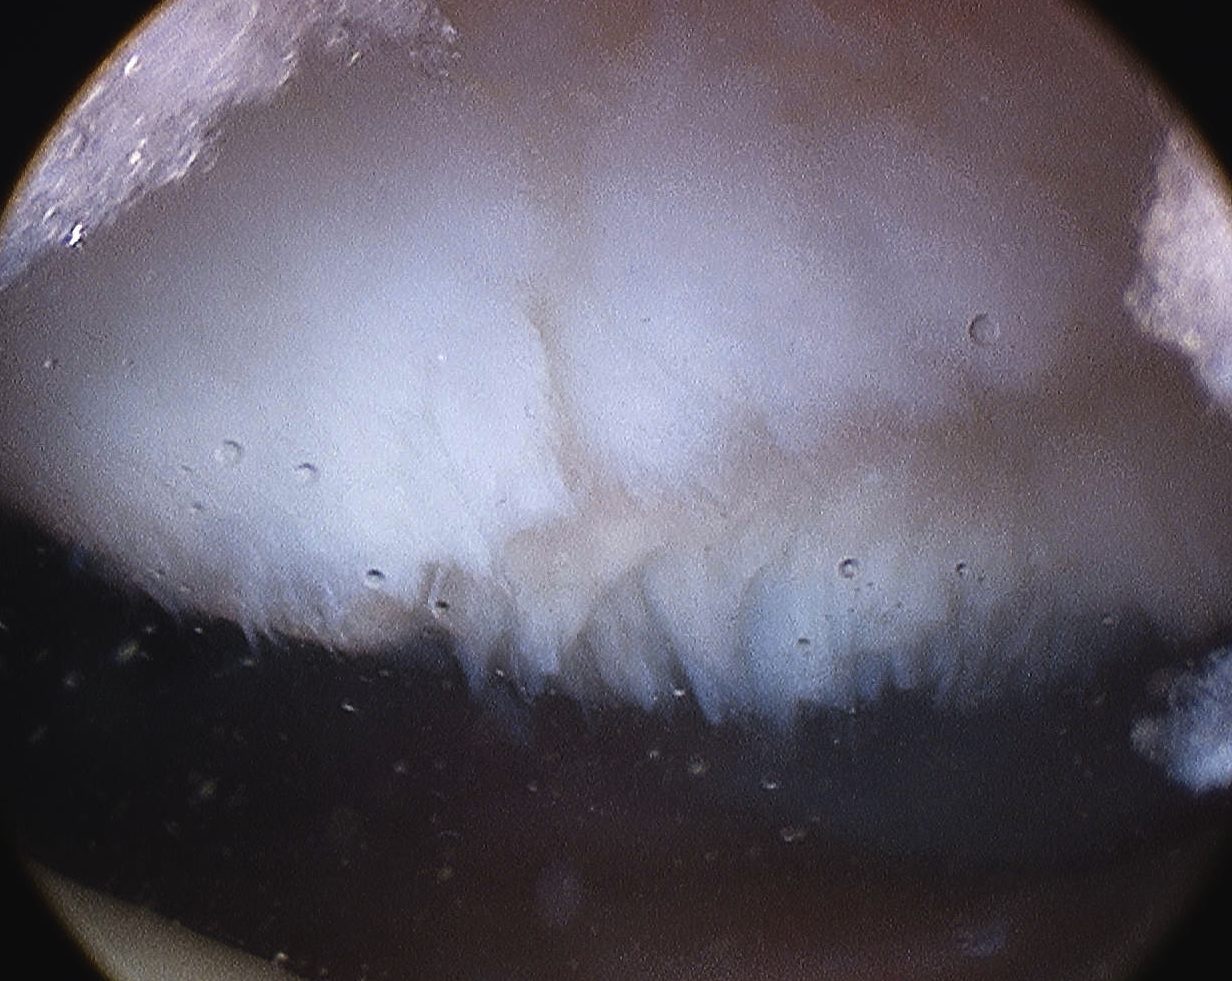

Microfracture of trochlea chondral defect

Debridement patella chondral flap

Debridement trochlea chondral damage